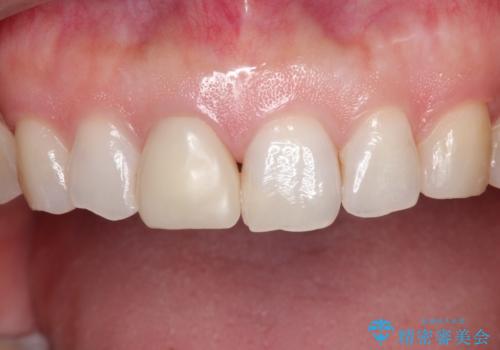

- 「他院で治療した前歯の被せものが一か月の間に2回外れたのでやり変えたい」を主訴に来院されました。

10年前に根管治療を他院で行っており、根尖性歯周炎の予防のため根管治療から行いました。被せものはオールセラミッククラウンで治療を行いました。

10年前にラバーダムシート無しに根管治療を行っており、現在、症状は出ていませんが、根尖性歯周炎の予防のため根管治療から行いました。ホームホワイトニングを2週間行って頂き、その後、オールセラミッククラウンで治療を行っています。